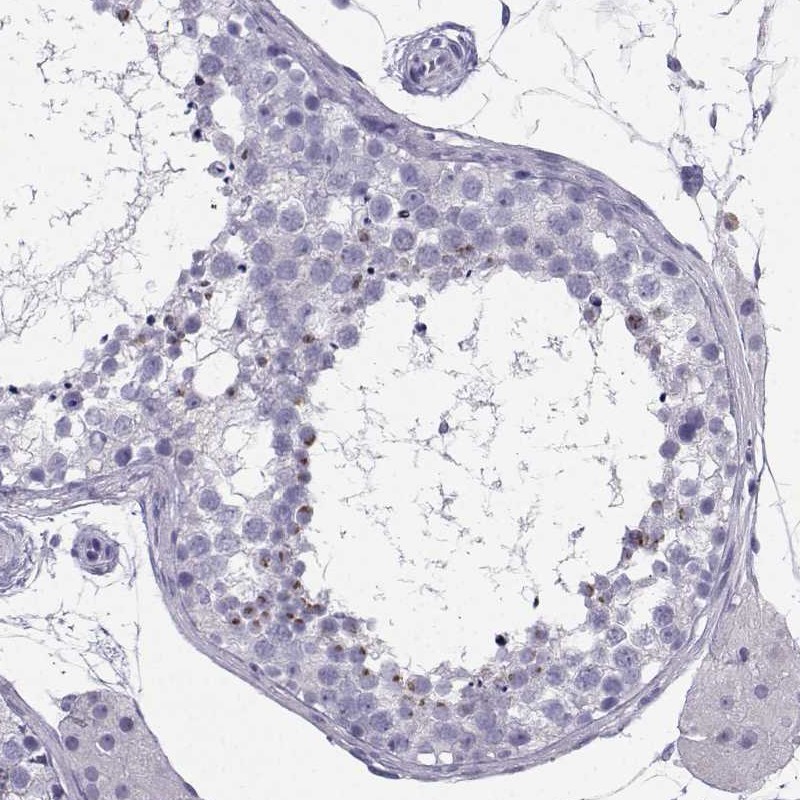

Immunohistochemical staining of human testis shows moderate nuclear positivity in cells in seminiferous ducts.